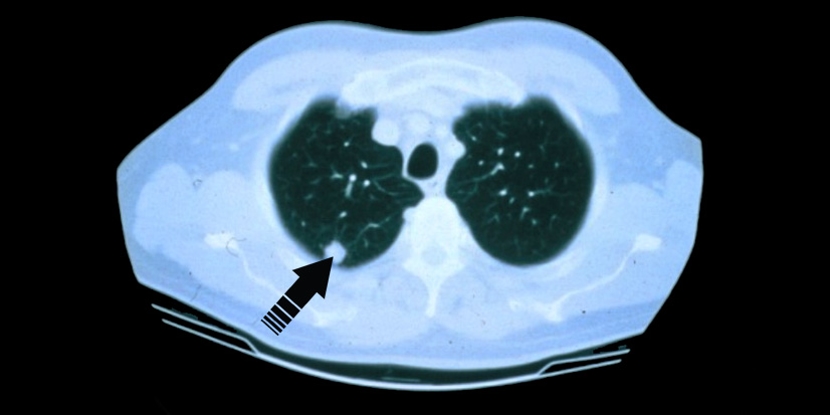

Prevention, then, may mean avoiding the items listed above (except family history, which cannot be controlled). For those individuals at a higher risk for lung cancer, a test called a Low-Dose CT scan, becoming known as the "mammogram" of lung cancer testing, available at the Independence Health System Lung Center.

Understanding the different types of lung cancer can help guide treatment decisions and outcomes. The two main types are non-small cell lung cancer (NSCLC) and small cell lung cancer (SCLC).

NSCLC is the most common type of lung cancer. It tends to grow and spread more slowly than small cell lung cancer. Subtypes include:

Adenocarcinoma, which often starts in the outer parts of the lungs and is more common in people who have never smoked.

Squamous cell carcinoma, typically found in the central parts of the lungs and more commonly linked to smoking.

Large cell carcinoma, which can appear in any part of the lung and tends to grow and spread quickly.

SCLC accounts for fewer lung cancer cases and tends to grow and spread more rapidly. It is strongly associated with smoking and often discovered at a more advanced stage.

Each type of lung cancer behaves differently and may require a unique treatment approach. That’s why early detection and proper diagnosis are so important.